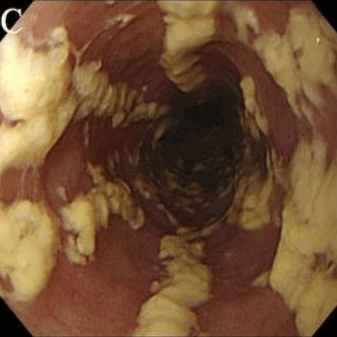

Эндоскопическая классификация кандидозного эзофагита по Kodsi

kandidoznyy_ezofagit.png   kandidoznyy_ezofagit.png

Степень I: Несколько приподнятых белесоватых бляшек размерами до 2 мм в диаметре, с гиперемией, но без отека или язв.

Степень II: Множественные приподнятые белесоватые бляшки размерами более чем 2 мм в диаметре с гиперемией вокруг, но без отека или язв

Степень III: Сливные линейные и узловатые приподнятые бляшки, с гиперемией и язвами

Степень IV: Те же изменения, что и при III степени, плюс контактная кровоточивость слизистой оболочки и иногда сужение просвета пищевода

• · Диагноз кандидозного эзофагита устанавливается, как правило, при эзофагоскопии, когда выявляются белые и белесовато-желтые бляшки и бляшкоподобные налеты на слизистой оболочке пищевода. Зачастую участки белесоватого налета носят диффузный характер, и покрывают всю поверхность слизистой оболочки пищевода.

• · Патогномоничным признаком кандидозного эзофагита является тот факт, что налет с трудом снимается биопсийными щипцами и после его удаления остаются участки осаднения слизистой оболочки.